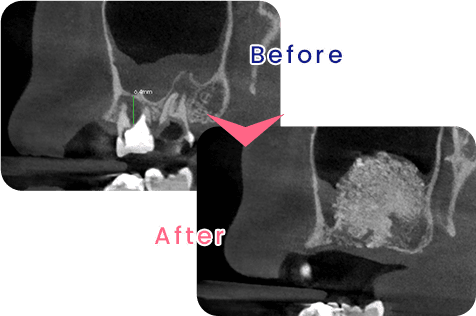

GBR(骨誘導再生法)と呼ばれる手術方法です。インプラントを顎の骨に埋め込む際、十分な骨の高さや厚みが必要になりますが、歯周病や加齢により顎の骨が不足している自家骨(自分の骨)や、人工的な材料を使用し、数ヶ月間の治療機関を経て骨が再生します。

患者様に、より多くの選択肢からご自身に合ったものをお選び頂きたいと考え、インプラント治療を実施しております。インプラントとは、歯を失った顎堤に人工歯根を埋め込み、人工歯を取り付ける治療です。

当院のインプラント治療